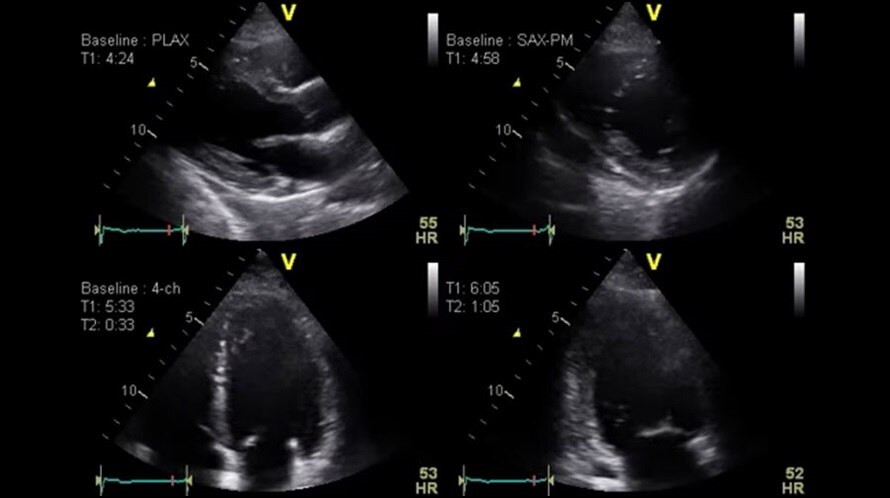

Режим цветового тканевого Доплера (TVI)

Отображает динамическую информацию от движущихся тканей сердца, позволяя с легкостью определять функцию левого желудочка.

Автоматически корректирует параметры для оптимизации рабочего процесса, повышения воспроизводимости и диагностической достоверности.

Опция автоматического отображения функции (AFI)

Позволяет рассчитать и количественно оценить продольную деформацию и движение стенок левого желудочка по технологии спекл-трекинга, а также оценить регионарную и глобальную функцию миокарда левого желудочка.